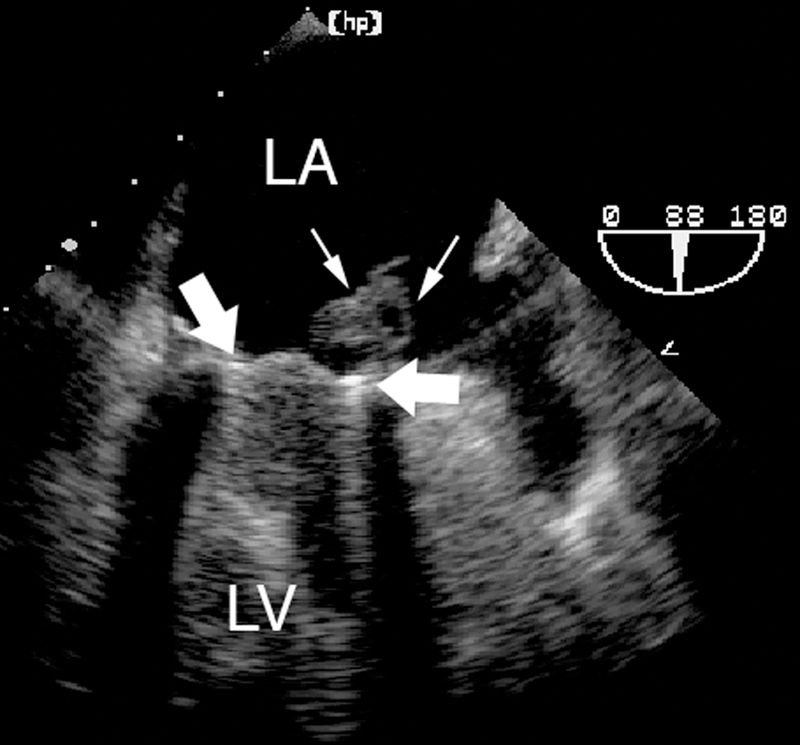

فحوصات تشخيصية لبعض امراض القلب والشرايين التاجية